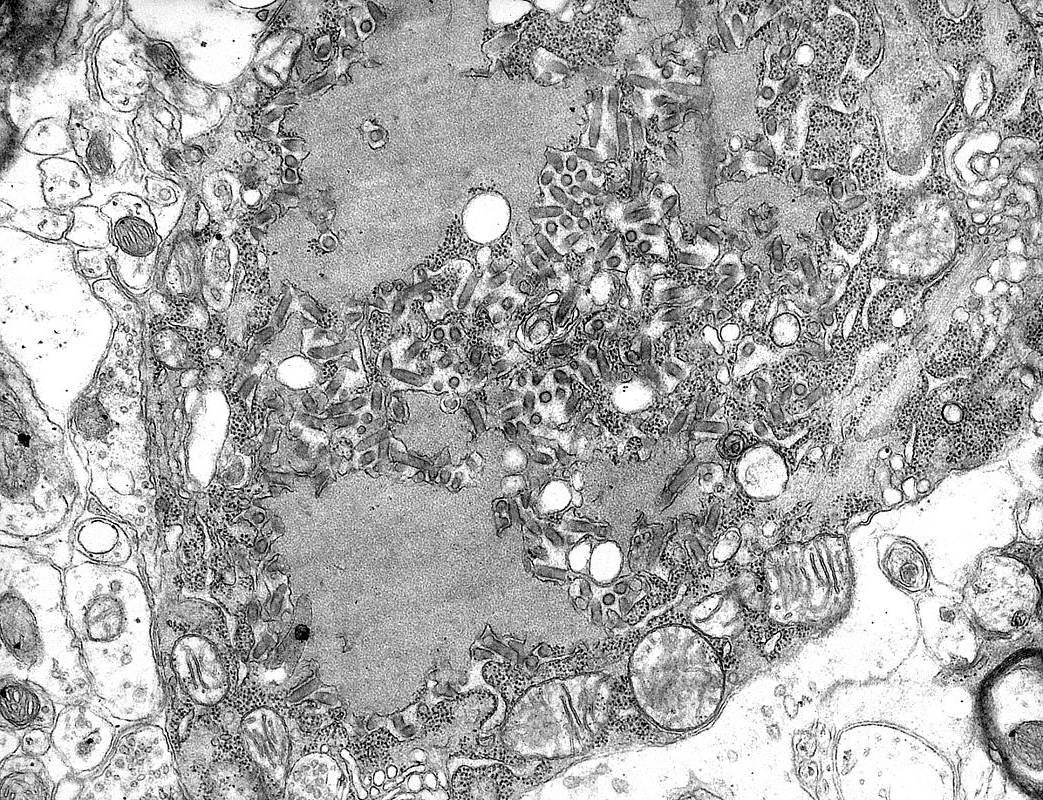

Бешенство

Электронная микрофотография

вируса бешенства

и новообразования в цитоплазме

нейронов головного мозга,

вызванные размножением

вируса.